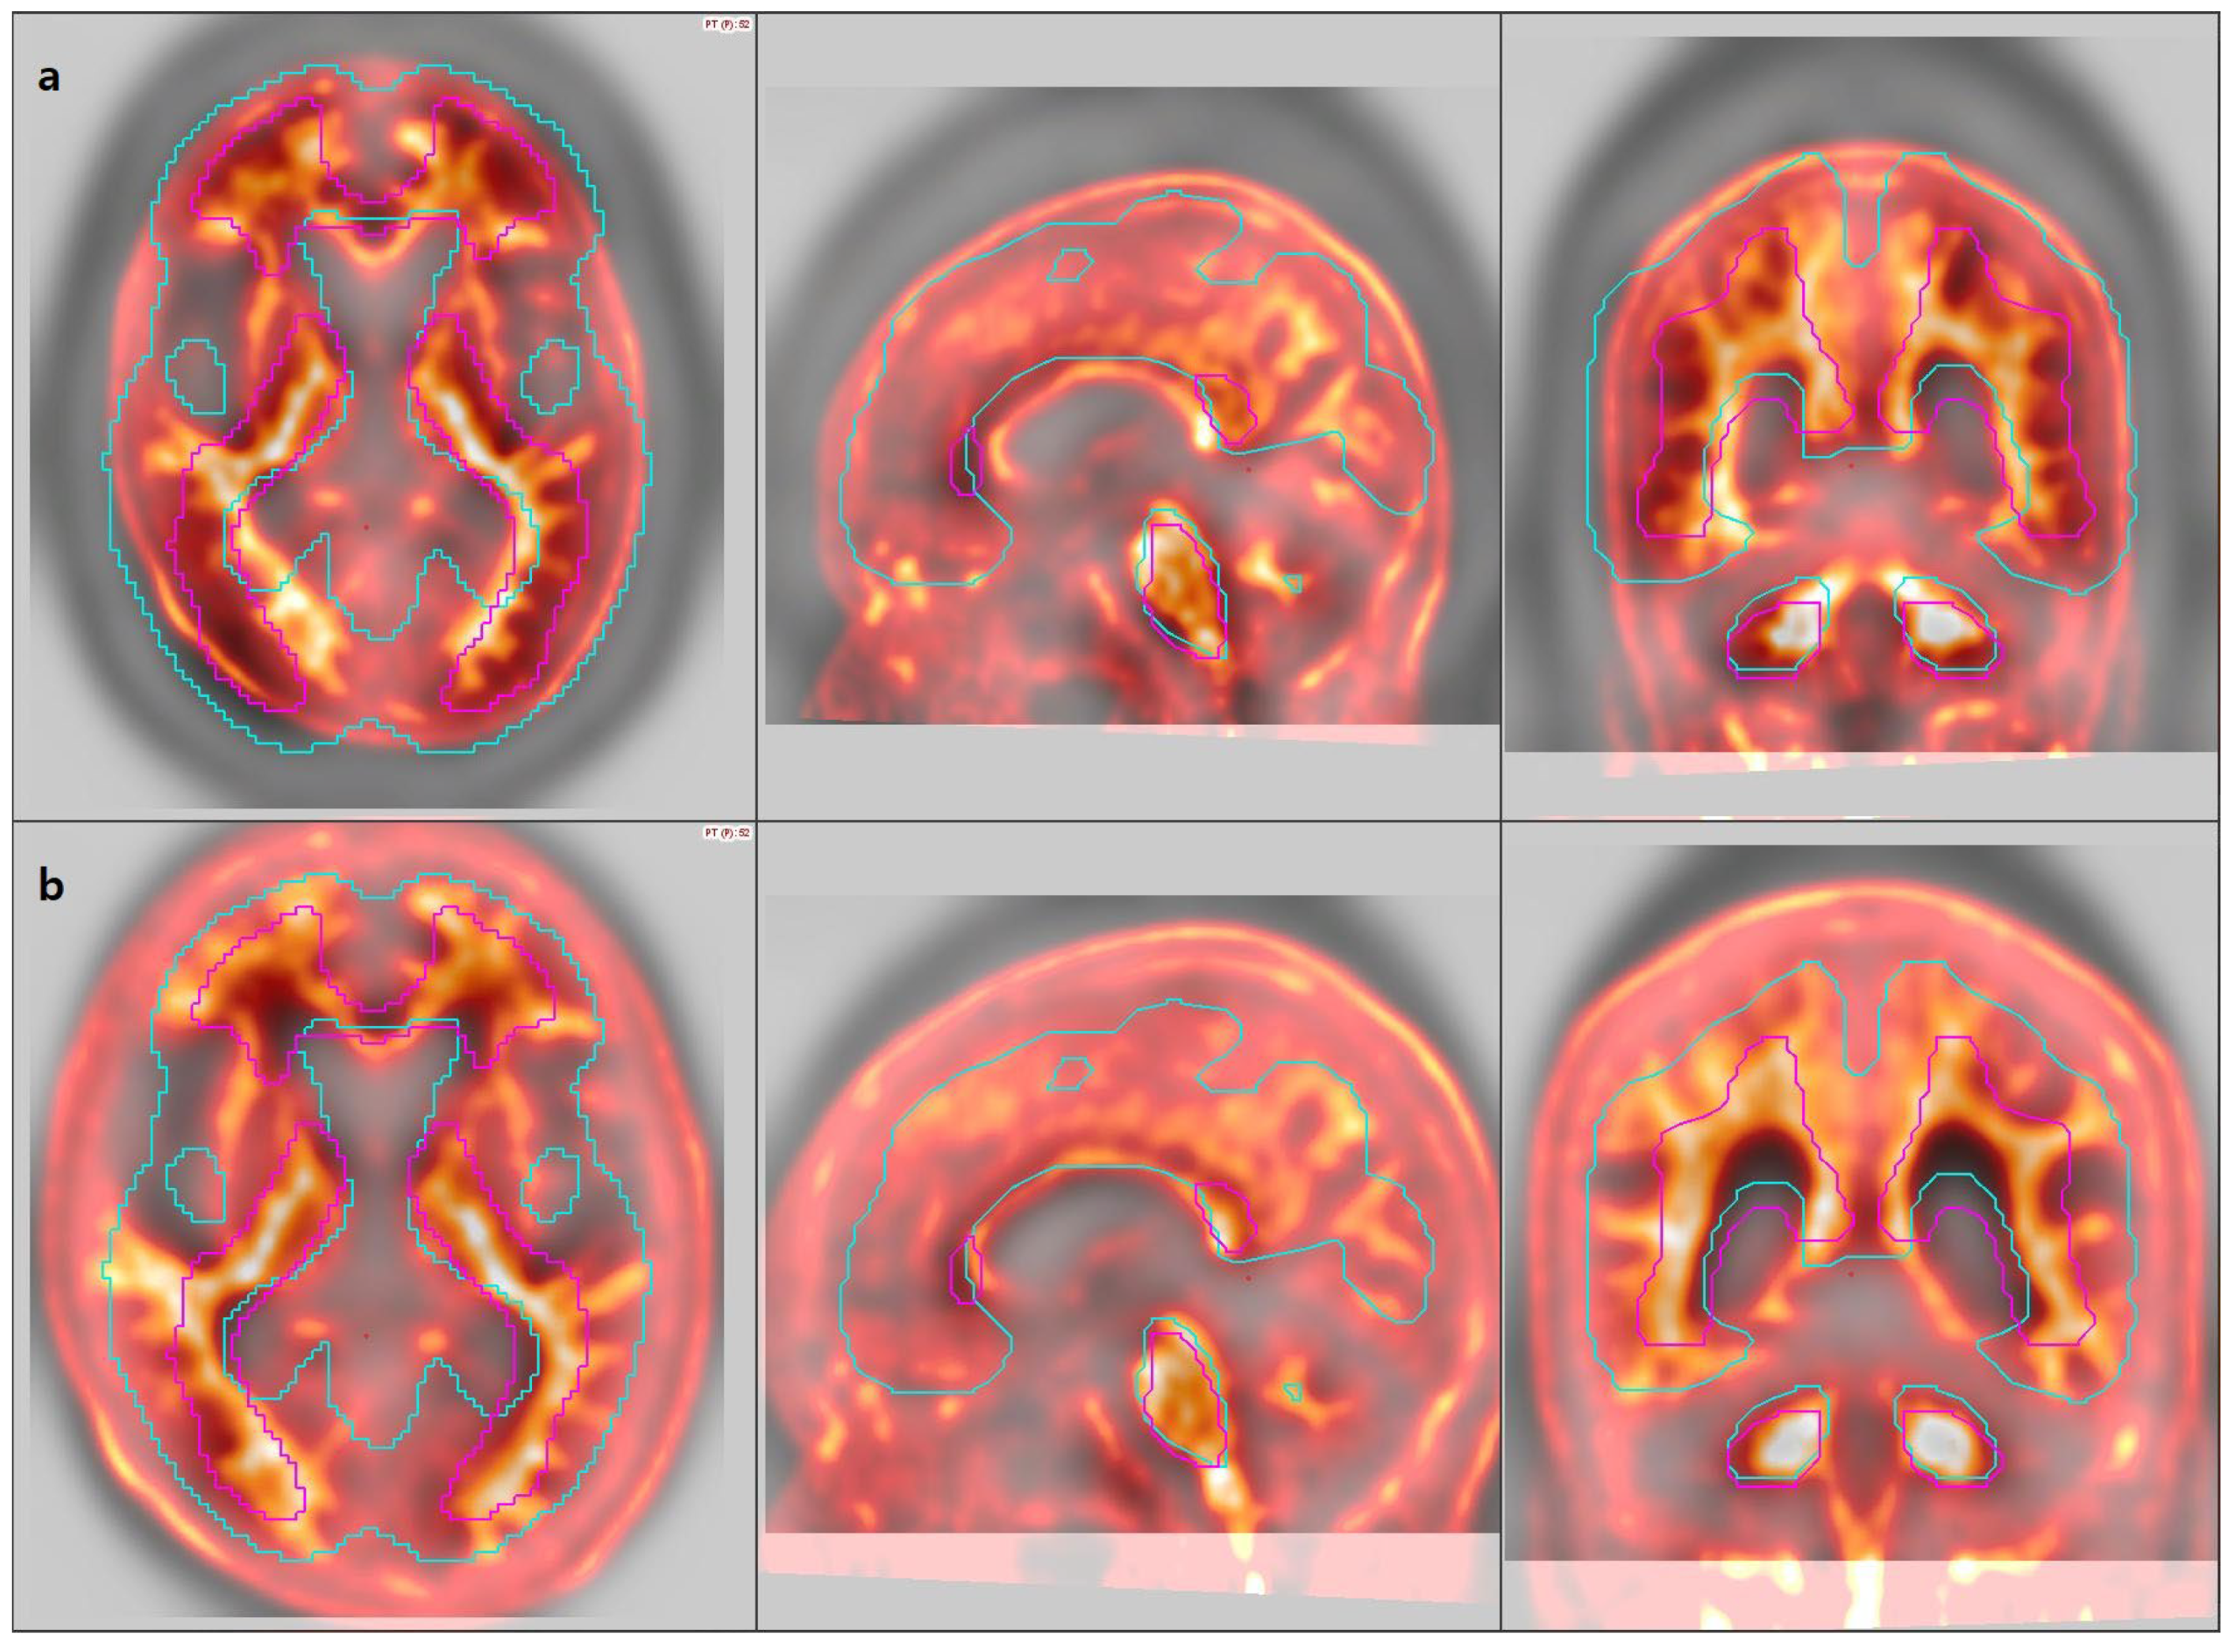

3.2. Image Analysis

3.3. Agreement Among Quantification Software